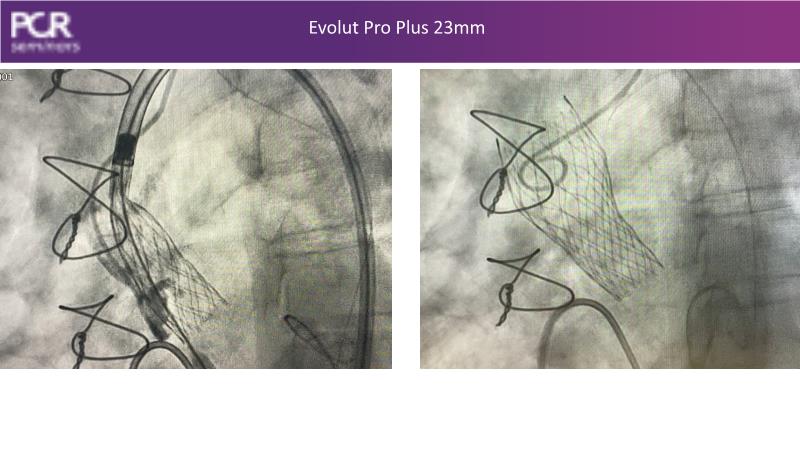

Watch this session to discover insights into patient-prosthesis mismatch and strategies to mitigate risks, delve into the significance of aortic valve commissure for coronary alignment optimization during TAVI, and explore solutions for common TAVI challenges such as peripheral vessel tortuosity and asymmetric valve calcifications in large or small aortic annuli.

- To discuss options to overcome common daily challenges of TAVI: peripheral vessel tortuosity, horizontal aorta, asymmetric valve calcifications in large, or in small aortic annuli